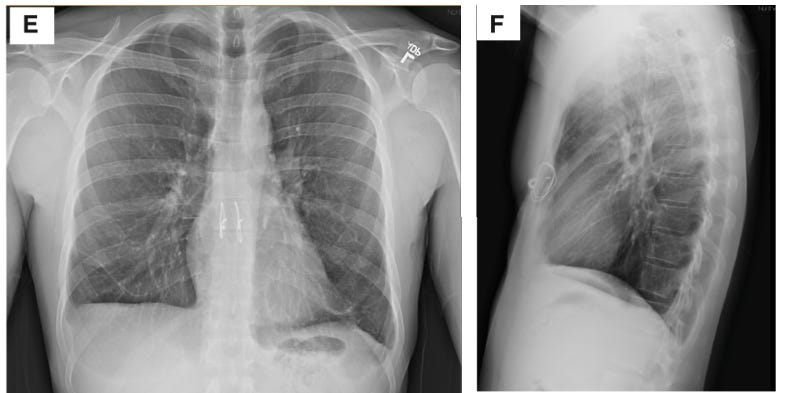

Un patient de 33 ans, atteint d’un syndrome de détresse respiratoire aiguë (SDRA) après une grippe B, a survécu 48 heures sans poumons grâce à une technique innovante. Son état, aggravé par une infection pulmonaire irréversible, nécessitait une ablation totale des poumons pour stopper la progression de la maladie. Une équipe médicale a alors utilisé une circulation extracorporelle pour oxygéner son sang et maintenir ses organes en vie, le temps qu’un greffon soit disponible.

Cette avancée montre qu’il est possible de stabiliser des patients en attente de greffe, même dans des cas extrêmes. Elle ouvre la voie à de nouvelles stratégies pour sauver des vies lorsque les traitements classiques échouent. Une lueur d’espoir pour les patients atteints de maladies pulmonaires graves.